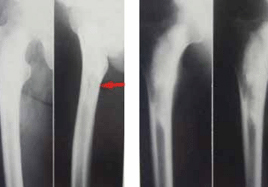

7.X線拍片早期無明顯改變、發病兩周左右方具骨破壞、增生和病理性骨折表現。

1.全身中毒症狀、高燒寒戰。局部持續性劇痛、乾骺端深壓痛、患肢呈“假性癱”,局部有深壓痛。2.白細胞總數增高、中性白細胞增高、血培養陽性。3.分層穿刺見膿液和炎性分泌物。4.X線拍片所示:兩周左右方有變化。